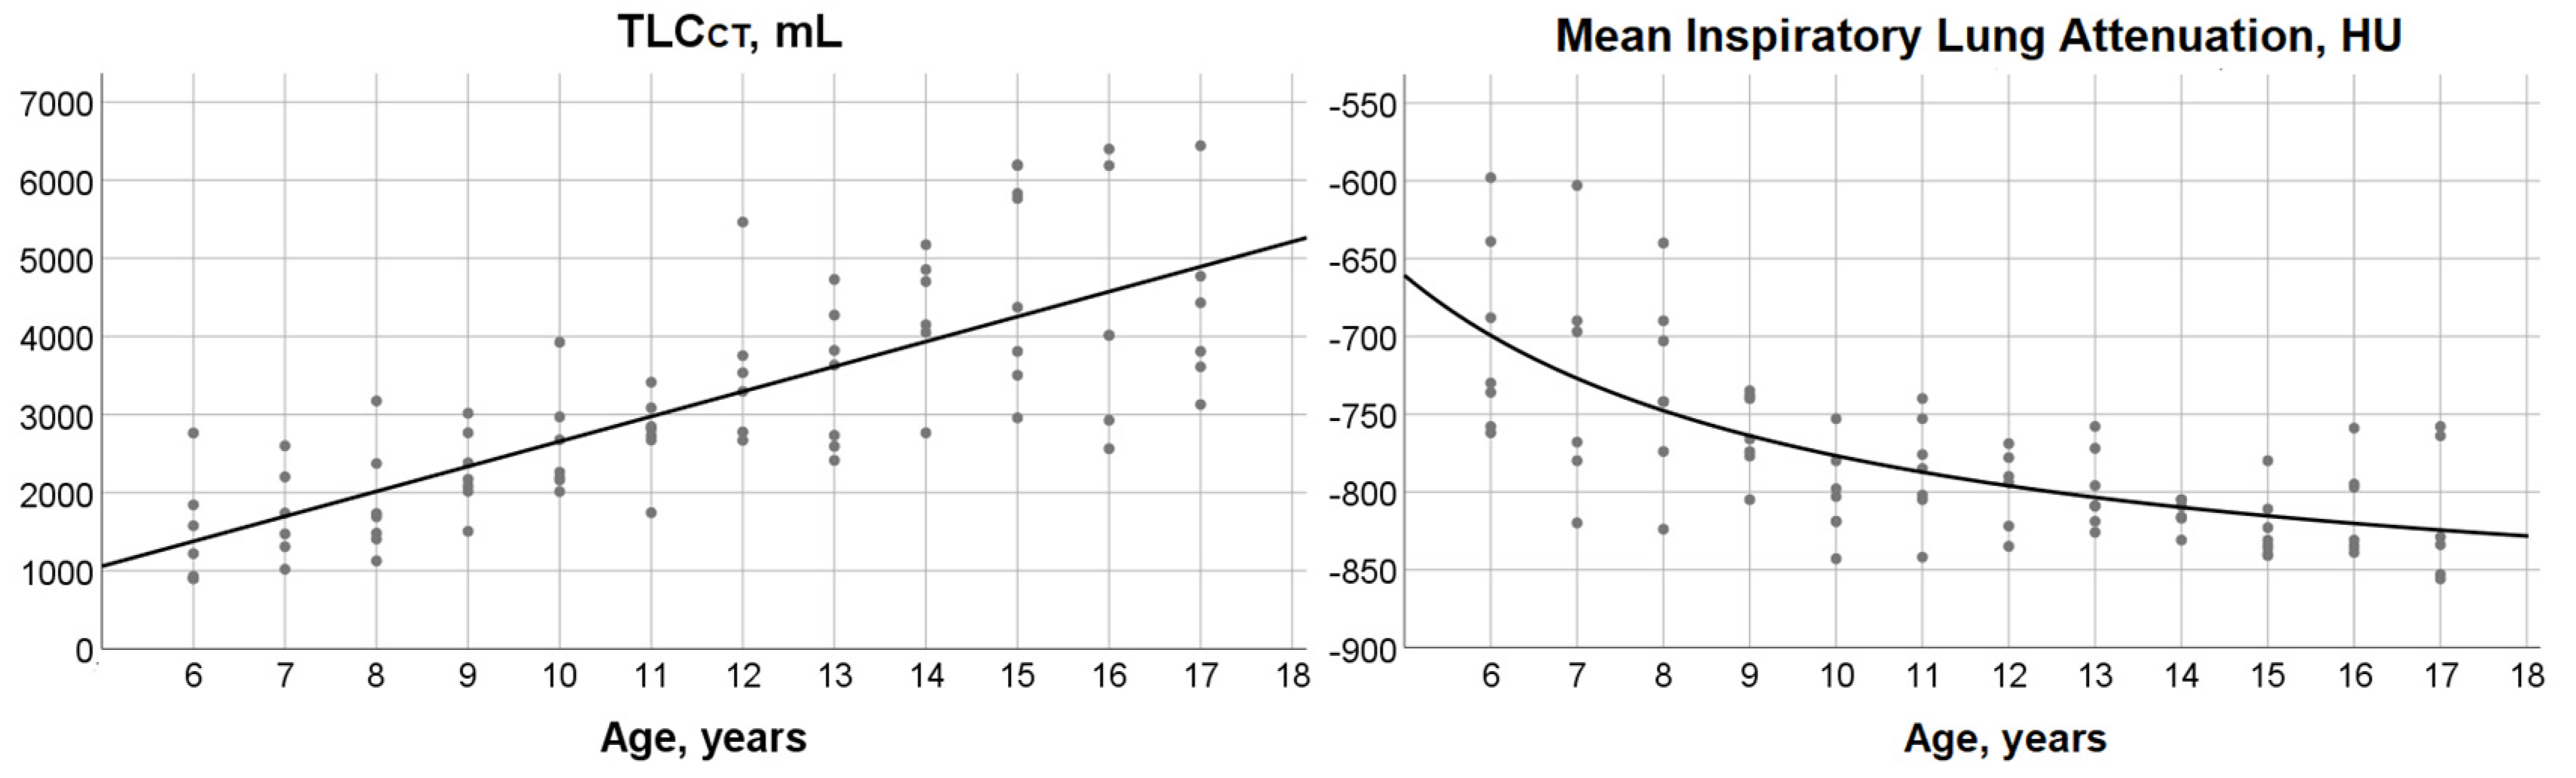

3.2. TLCCT, Mean Lung Attenuation at Full Inspiration and Their Relationship with Age

3.3. Age-Dependence of Low and High Attenuation Thresholds